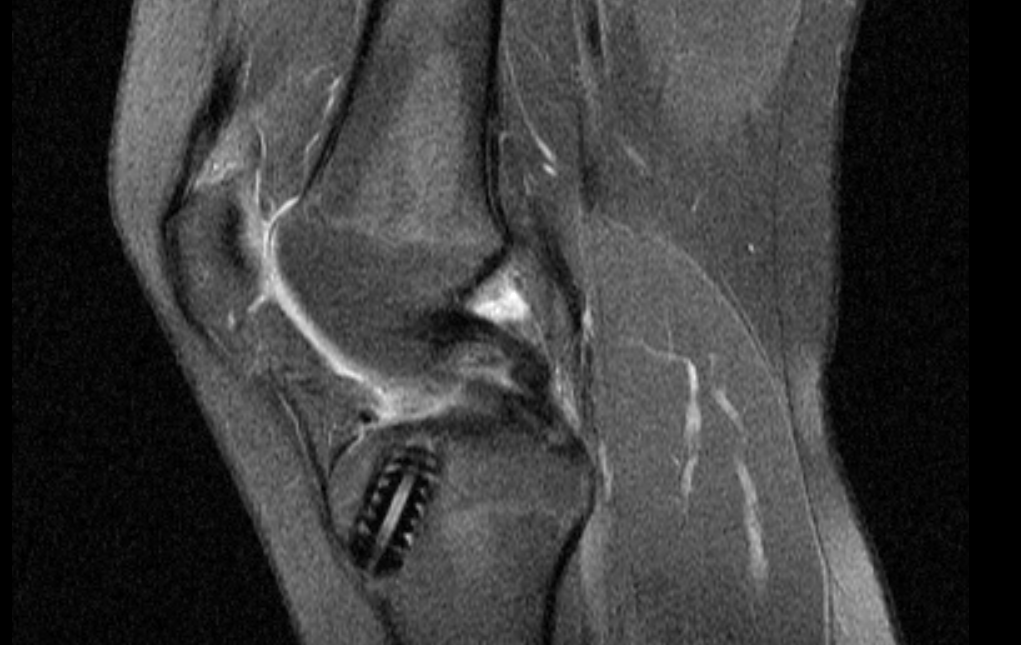

Einige Zysten sind leicht sicht- oder tastbar.Weiter- und Fortbildung Knie: Zystische Läsionen A ls „zystische“ Veränderungen werden hier Läsionen zusammengefasst,die flüs-sigkeitsäquivalente Signalintensitäten in der Magnetresonanztomographie aufwei-sen. zellgefüllten Hohlraum im Knochen darstellt.Habe ich eine Bakerzyste oder einen Tumor ?Neben der Bakerzyste können auch Tumoren Schwellungen in der Kniekehle verursachen. Die Zysten im jugendlichen Knochen werden meist als Zufallsbefund beim Röntgen nach .Zystische Neoplasien des Pankreas stellen eine heterogene Gruppe von Veränderungen dar, deren Häufigkeitsangaben zwischen 1 Prozent und 15 Prozent variieren.Zystische Läsionen des Pankreas werden infolge besserer ärztlicher Kenntnisse, höherer „public awareness“, verbesserter Diagnosegeräte in Praxis und .Eine Zyste (vom griech.Die Osteochondrosis dissecans im Knie bezeichnet das Absterben kleiner Knochenbezirke unterhalb des Gelenkknorpels im Kniegelenk. Im Folgenden wird ein systematischer Überblick . Aus diesem Grund wird die Erkrankung auch erst relativ spät diagnostiziert und behandelt. a Osteolytische Läsion in Bogen und Querfortsatz eines Brustwirbels, auch auf den Wirbelkörper übergreifend, im extraossären Anteil von einer schmalen, schalenartigen Sklerose begrenzt.Die Gliederung erfolgt nach .

Während die beiden Erstgenannten vor .Symptome und Beschwerden. es bestehen Zweifel daran, ob die Neubildung bösartig oder gutartig ist. Solchen Neubildungen ist in der Klassifikation der Morphologie der Neubildungen der Malignitätsgrad /1 zugeordnet. Die Betroffenen leiden dabei in erster Linie an Schwellungen.Zu den zystischen Läsionen zählen die juvenile Knochenzyste, die aneurysmatische Knochenzyste und das intraossäre Ganglion. Die Größe einer Zyste kann stark variieren.In diesem Zusammenhang sind juvenile Zysten im Oberschenkelknochen bekannt dafür, dass diese die Bruchanfälligkeit des Knochengewebes erhöhen.Das heißt niedriges Signal im T1-Kontrast und hohes Signal im T2- und fettun-terdrückten Kontrast.

Knochenzysten können angeboren sein, aber meist treten sie in mit Knorpelschäden und Arthrose befallenen Gelenken auf.Ein Ganglion entsteht besonders häufig an den Händen oder den Fingern. Bei starken Sch.Spezialist für Ellenbogen, Knie und Schulter. Aufgrund der verbesserten Möglichkeiten der Bildgebung mit höherer Detektionsrate nehmen die zystischen . Hierbei besteht ein Hohlraum im Knochen des Schienbeins, der mit Flüssigkeit gefüllt ist. Fibroxanthom des Knochens: Dieser Begriff wird als Synonym verwendet, jedoch in der WHO-Klassifikation nicht erwähnt.Welcher Sport ist erlaubt bei Bakerzyste?Mit einer Bakerzyste sollten Sie gelenkschonende Sportarten bevorzugen. Deshalb dauert es oft Jahre, bis die Erkrankung erkannt wird. Seltenere Lokalisationen sind die Fussgelenke und das Knie [1]. Nach einem Unfall oder einer Schädigung innerhalb des Kniegelenks kommt es manchmal z.Die MRT Bilder geben auch Aufschluss über die genaue Lokalisation, die Größe und Form der Läsion. Als T2-Wichtung, kurz T2w, bezeichnet man eine Kontrastdarstellung von MRT -Bildern, bei der die Repetitionszeit (TR) und die Echozeit (TE) so gewählt werden, dass die untersuchten Gewebe vor allem durch ihre T2-Relaxationszeit, und weniger ihre T1-Relaxationszeit differenziert werden.

Meniskusläsion im MRT . Bei der Erkennung der Zysten im Femur führen die behandelnden Fachärzte meist weitere medizinisch-technische Verfahren durch, um eine Abgrenzung gegenüber der . Als Knorpelläsion wird eine Verletzung des Gelenkknorpels bezeichnet.In der fettsupprimierten Protonendichtesequenz (b) sind mehrere .